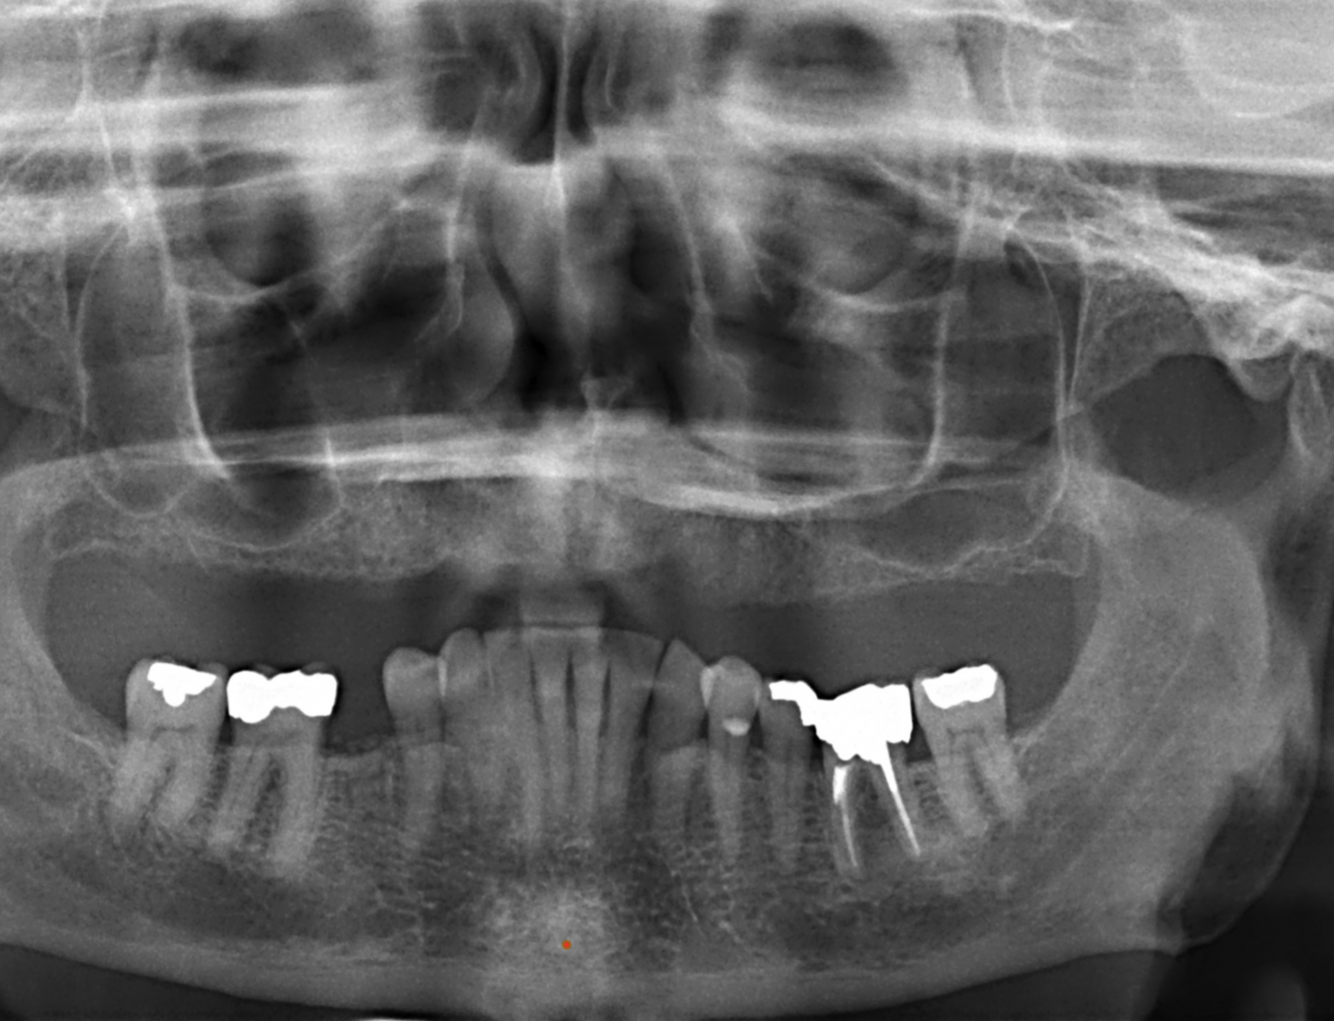

What is seen in the following image?

Hyoid bone

49

What is indicated by the red in the following image?